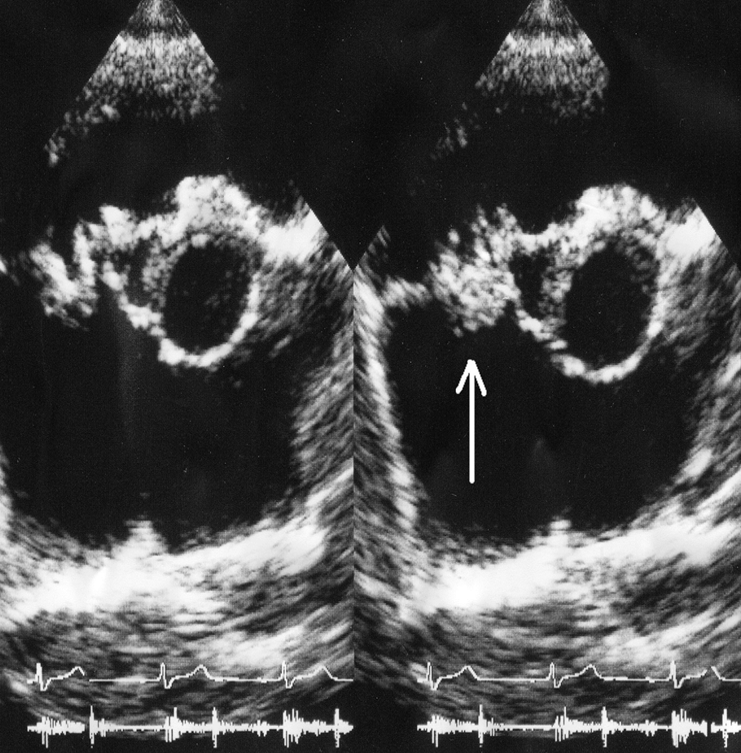

what is seen here?

tricuspid valve vegetation w/ severe regurg